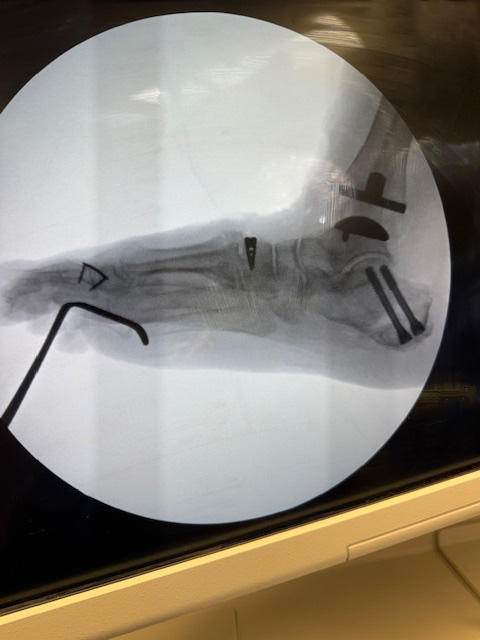

Dr. Stoddard evaluated my ankle, my desire to increase mobility and reduce the chronic pain. After several consults with other Orthopedics to discuss my ankle and its ‘current’ condition – Frozen bone mass, Dr. Stoddard recommended a total ankle replacement.

Dr. Stoddard discussed the entire procedure with me – Up and downsides – Best case – No pain and good range of movement for the entire foot and ankle – system. Worst case – I’d be a Pirate with a nice Peg-leg on the left side. ‘Spinning’ would NOT be a problem, dancing would be… Luckily the better of the two cases prevailed. I had the total ankle replacement completed by Dr. Stoddard and his team at SOCO. My recovery has been a challenge, (self-inflicted – When the Dr. tells you to do or NOT do something, listen and follow direction.),… a little longer than I had hoped. I am now walking, pain free, I’m still in Physical Therapy, working on range of motion and re-building leg/foot muscle. The recover for me was a little longer than normal or expected due to my past ankle history and infections…and I pushed the process, a little harder than I should have – Hind sight is always 20/20.

I would recommend Dr. Stoddard without reservation. Dr. Stoddard completed an extremely complicated and lengthy ankle replacement as promised. Immediately after surgery I had NO pain or discomfort in the ankle or foot, for the first time in nearly 4 years.